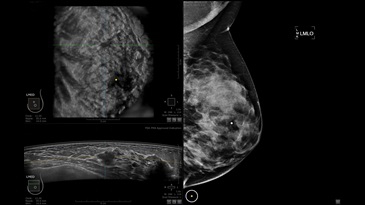

GE INVENIA ABUS – это современный УЗИ аппарат, который создан для точной и эффективной диагностики сканирования с высокой плотностью молочных желез. Выявляемость патологий раковых и предраковых стадий заболевания составляет 55%, что в конечном счете позволяет ставить врачу точные и своевременные диагнозы. Традиционные методы использования маммографии не показывают такой выявляемости, ограничиваясь лишь 3-38%.

УЗИ-аппарат GE INVENIA ABUS позволяет проводить максимально операторонезависимые процедуры, что значительно снижает риск неправильной постановки диагноза и сопутствующие издержки на обработку информации. Система готовит отчет в течение 3-х минут после сканирования, это безусловное преимущество по сравнению с обычным УЗИ сканером.

Данное устройство классифицируется, как стационарное, используемое в многопрофильных клиниках, женских консультациях, медицинских центрах. Вес без учета дополнительного оборудования составляет 105 кг. Удобная колесная база позволяет оперативно маневрировать в ограниченных пространствах, в том числе передвигать устройство в коридорах клиники. Большой 17-ти дюймовый монитор с широкими углами обзора выводит максимально качественную картинку в формате Full HD.

• Отображение объемных 3D ультразвуковых изображений, которые состоят из традиционных поперечных и воссозданных коронарных и сагиттальных проекций

• Стандартизованная ориентация изображения: «толстый срез» в коронарной плоскости; поперечная; сагиттальная плоскость; радиальный и антирадиальный поворот изображения; просмотр исключительно области интереса